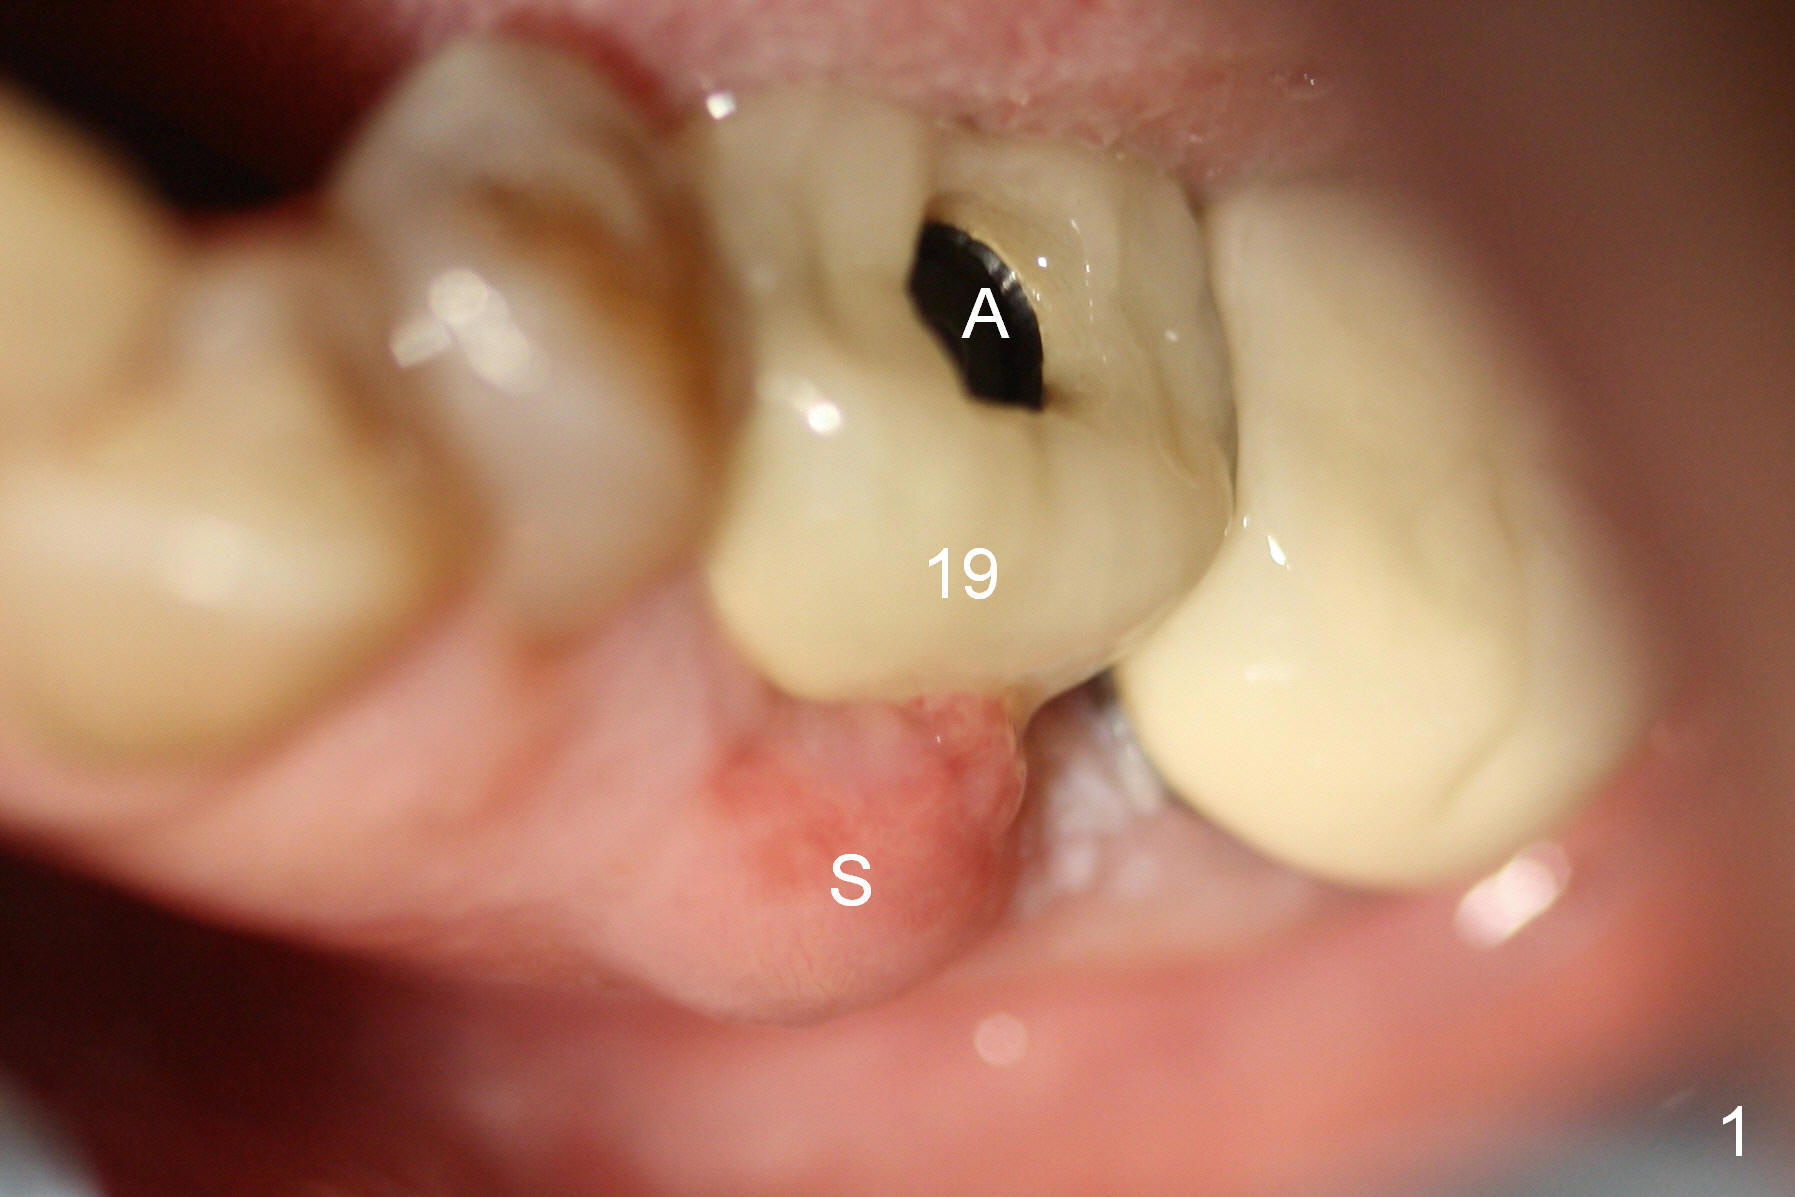

A 47-year-old lady lives out of town and presents to clinic with chief complaint "lower left back tooth easily bleeding with food impaction". Dental history and examination reveals failure of endo retreat of the tooth #19 (Fig.1), buccal gingival swelling (S), open access (A) and furcal and mesial periapical radiolucency (Fig.2 *). She is pleased to know availability of immediate implant and immediate provisional and accepts and receives the treatment at the same visit. The immediate implant (tissue-level) is designed to be as large as 7 mm and as long as 17 mm (Fig.3). To reduce paresthesia (yellow dashed line: the possible upper border of the Inferior Alveolar Canal)), a shorter implant (14 mm long in red line) is preferred. The tooth is extracted with sectioning. Granulation tissue is removed from the furca. The buccal plate appears to be intact. The septum is flat (Fig.4,10a S). Osteotomy starts in the middle of the septum with a 1.2 mm drill (Fig.10b red circle). As osteotomy increases in diameter (Fig.5 O), the apical end appears to be deviated mesiobuccally (Fig.10c large red circle). When a 6x17 mm tapered tap is being placed 14 mm deep (Fig.6 T), vibration of the buccal plate is seemingly felt at the apex (Fig.10d green circle). Further osteotomy may perforate the buccal plate. A 6x14 mm tissue-level implant is placed with >60 Ncm of insertion torque (Fig.7,8 I), followed by a 5x3 mm abutment (A) and bone graft (* in the remaining socket gap). An immediate provisional is cemented without occlusal contact (Fig.9 P).